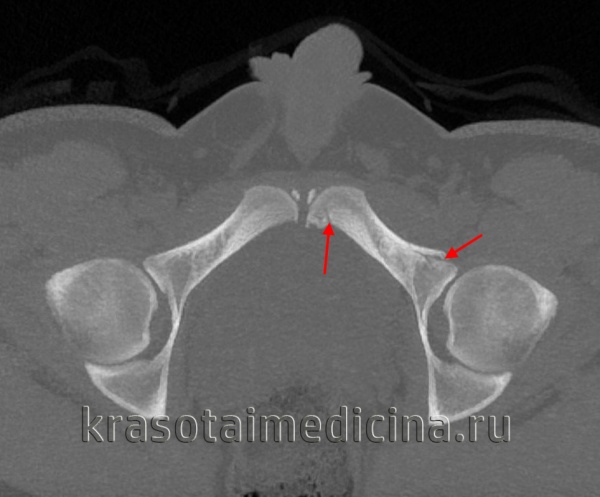

Рентгенография таза помогает уточнить диагноз, однако в ряде случаев снимков не достаточно для достоверного подтверждения перелома таза, поскольку линию перелома бывает трудно отличить от зоны роста. При возникновении затруднений пациента направляют на МРТ или КТ костей таза. Консультации других специалистов, как правило, не нужны.

Для уточнения диагноза выполняют обзорную рентгенографию таза и рентгенографию поврежденного сустава в трех дополнительных проекциях. По возможности пациента направляют на КТ таза, поскольку эта методика позволяет более точно оценить тяжесть травмы и характер смещения отломков. Диагностическая ценность компьютерной томографии возрастает при повреждениях задней колонны и оскольчатых переломах.